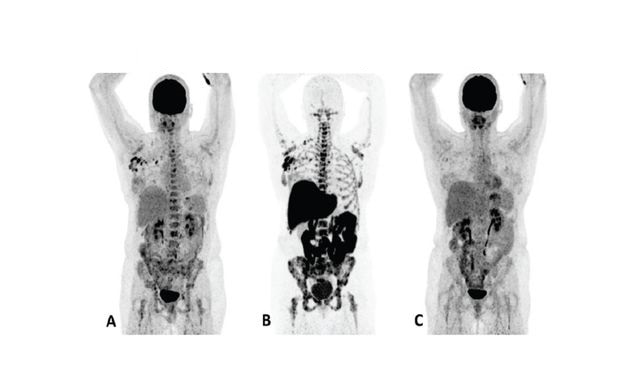

F18 fluoroestradiol and FDG PET images in a MBC treatment responder and non-responder*†15

Patient 1 (anterior/superior) responded to treatment with an AI and a CDK 4/6 inhibitor*15

Upper row responder: Baseline FDG PET (A) showed pathological uptake in axillary lymph nodes (right side) and in nearly all vertebrae and pelvic bones. Image B showed the baseline F18 fluoroestradiol PET with pathological ER expression in the axial skeleton (including vertebrae, pelvic bones, proximal humeri and femora) and in axillary lymph nodes (right side). After 8 weeks, the FDG PET (C) showed almost complete metabolic response (just some slightly elevated uptake in the axillary lymph nodes). The patient had been on treatment for more than 70 weeks. Lower row non-responder: Baseline FDG PET (D) showed pathological uptake in multiple skeletal lesions. Image E showed the baseline F18 fluoroestradiol PET with only some increased ER expression in thoracic vertebrae. After 8 weeks, the FDG PET (F) showed no metabolic response, even some increase in the pathologic uptake in the multiple skeletal lesions.15

Images from a prospective, single center, feasibility study that aimed to explore whether baseline F18 fluoroestradiol PET discordance and F18 fluoroestradiol uptake were correlated with outcome and response to concomitant treatment with an AI and a CDK 4/6 inhibitor. Thirty patients with ER+ MBC were included in the study, including 87% who received at least one previous line of ET in the metastatic setting.15